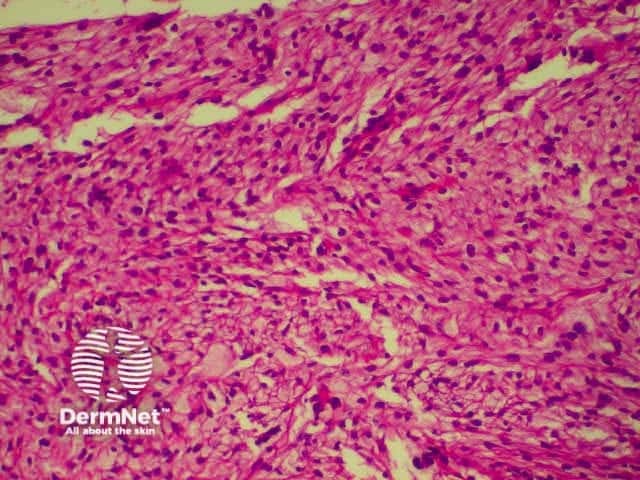

This is a tumour that has conflicting clinical and histological features. Clinically, this is a tumour of the elderly arising in sun damaged skin. Histologically, there is severe nuclear atypia with many mitotic figures and features of a sarcoma located in the superficial and mid dermis.

The histological diagnosis is one of exclusion following immunohistochemistry, as spindle cell squamous carcinomas, melanomas and leiomyosarcomas may all appear similar. It is possible that this lesion's good prognosis is simply due tits superficial location, rather than its cell of origin, but the features are well recognised and the prognosis well documented so that its retention as a specific entity appears justified.

pathology of atypical fibroxanthoma